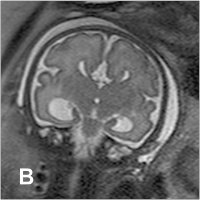

Fetus - 30. SSW

Abbildung 2a-b: SSW 30, Fetus mit Balkenagenesie, A. Medianes Schnittbild: Fehlender Balken, radiäre Gyrierung an der Medialfläche der Hemisphäre. Der Aquädukt und die Vierhügelplatte unauffällig. Der Hirnstamm zeigt dorsal dünklere Signale als ventral, was der normalen, dort bereits in dieser SSW vorhandenen Myelinisierung entspricht. Im Profil geringe Retrognathie. B. Frontales Schnittbild. Typische Konfiguration der Seitenventrikel, die aufgrund der medial der Vorderhörner erkennbaren Probst’schen Bündel weit auseinander stehen. In den erweiterten Temporalhörnern erkennt man eine nahezu senkrecht stehende Hippokampusformation, was einer Malrotation entspricht. Die Gyrierung ist symmetrisch, eine pathologische Konfiguration des frontalen Anteils des Gyrus cinguli, wie sie im Rahmen der Balkenagenesie zu erwarten ist, besteht. Intrazerebral ist die zelldichtere und daher dünklere Stammganglienregion von der helleren weißen Substanz, die ebenfalls in entwicklungsbedingt unterschiedliche Graustufen gegliedert ist, abgrenzbar.